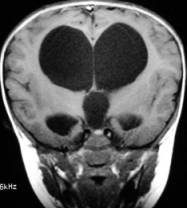

脑积水儿的产前早期诊断是预防脑积水儿出生的重要途径。由于明显的脑积水,在孕12——18周即可通过B超查出,所以要加强B超在产前诊断中的应用,及早终止妊娠,预防脑积水儿的出生,降低先天性脑积水的出生率。